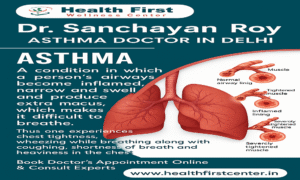

When it comes to respiratory health, asthma is one of the most prevalent and persistent […]